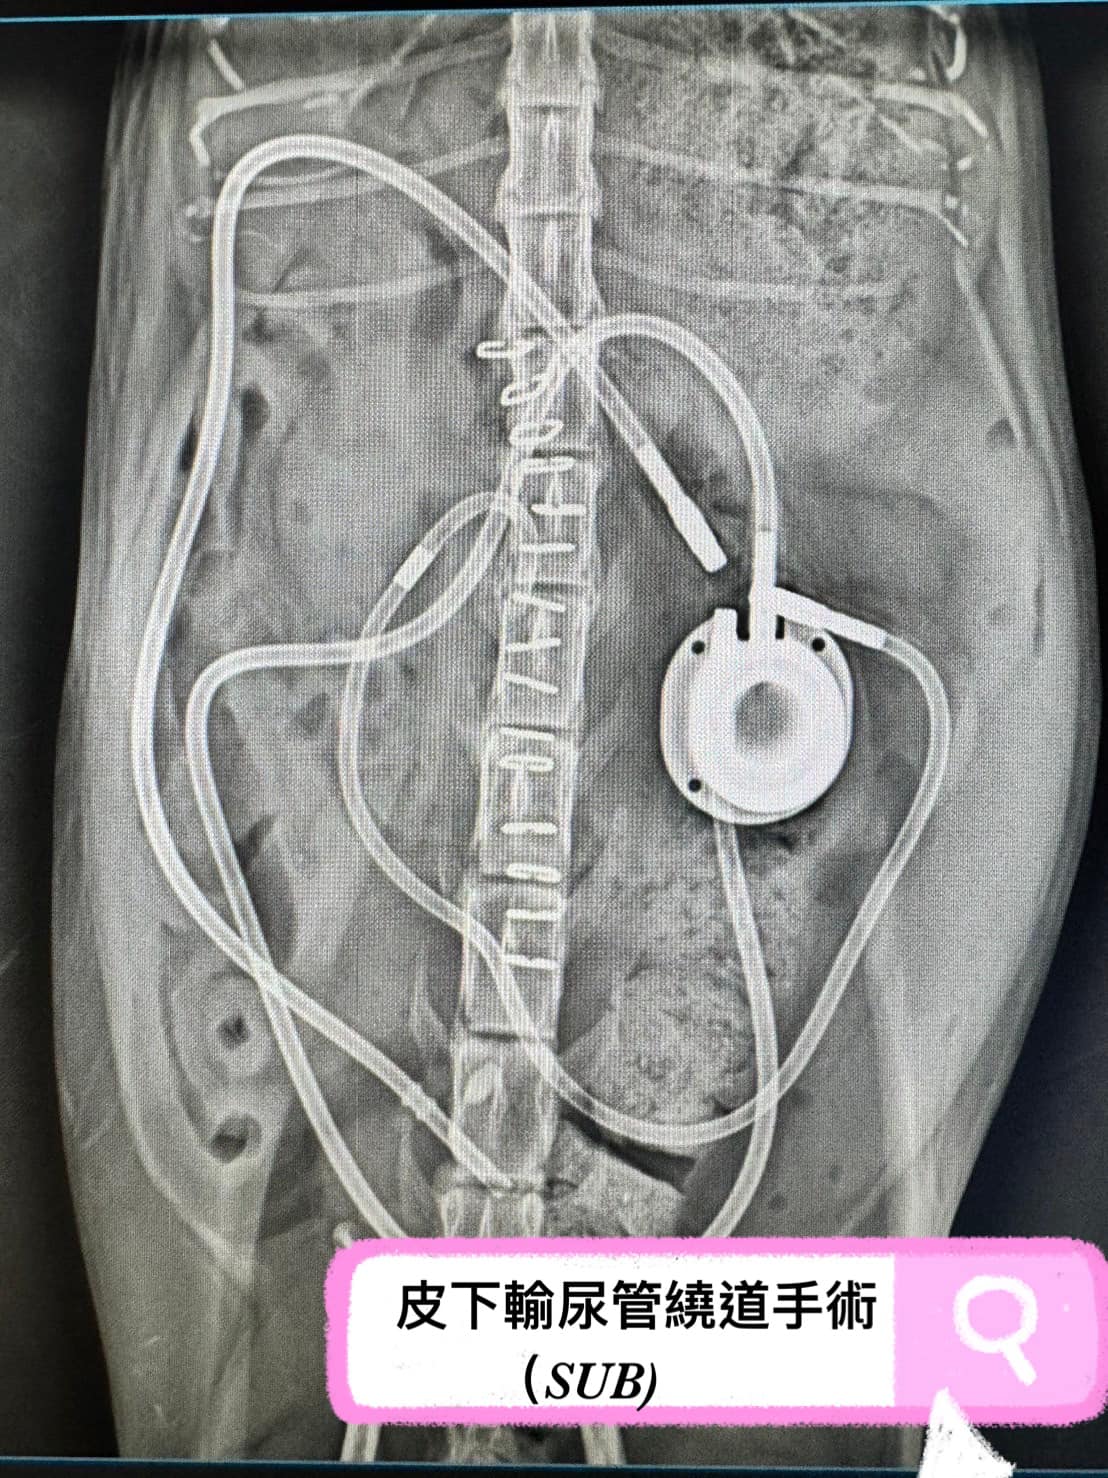

#皮下輸尿管繞道手術(SUB)

皮下輸尿管繞道手術也可簡稱為SUB

✔可銜接腎臟與膀胱,取代輸尿管的功能

✔後續仍須定期回診保養管路